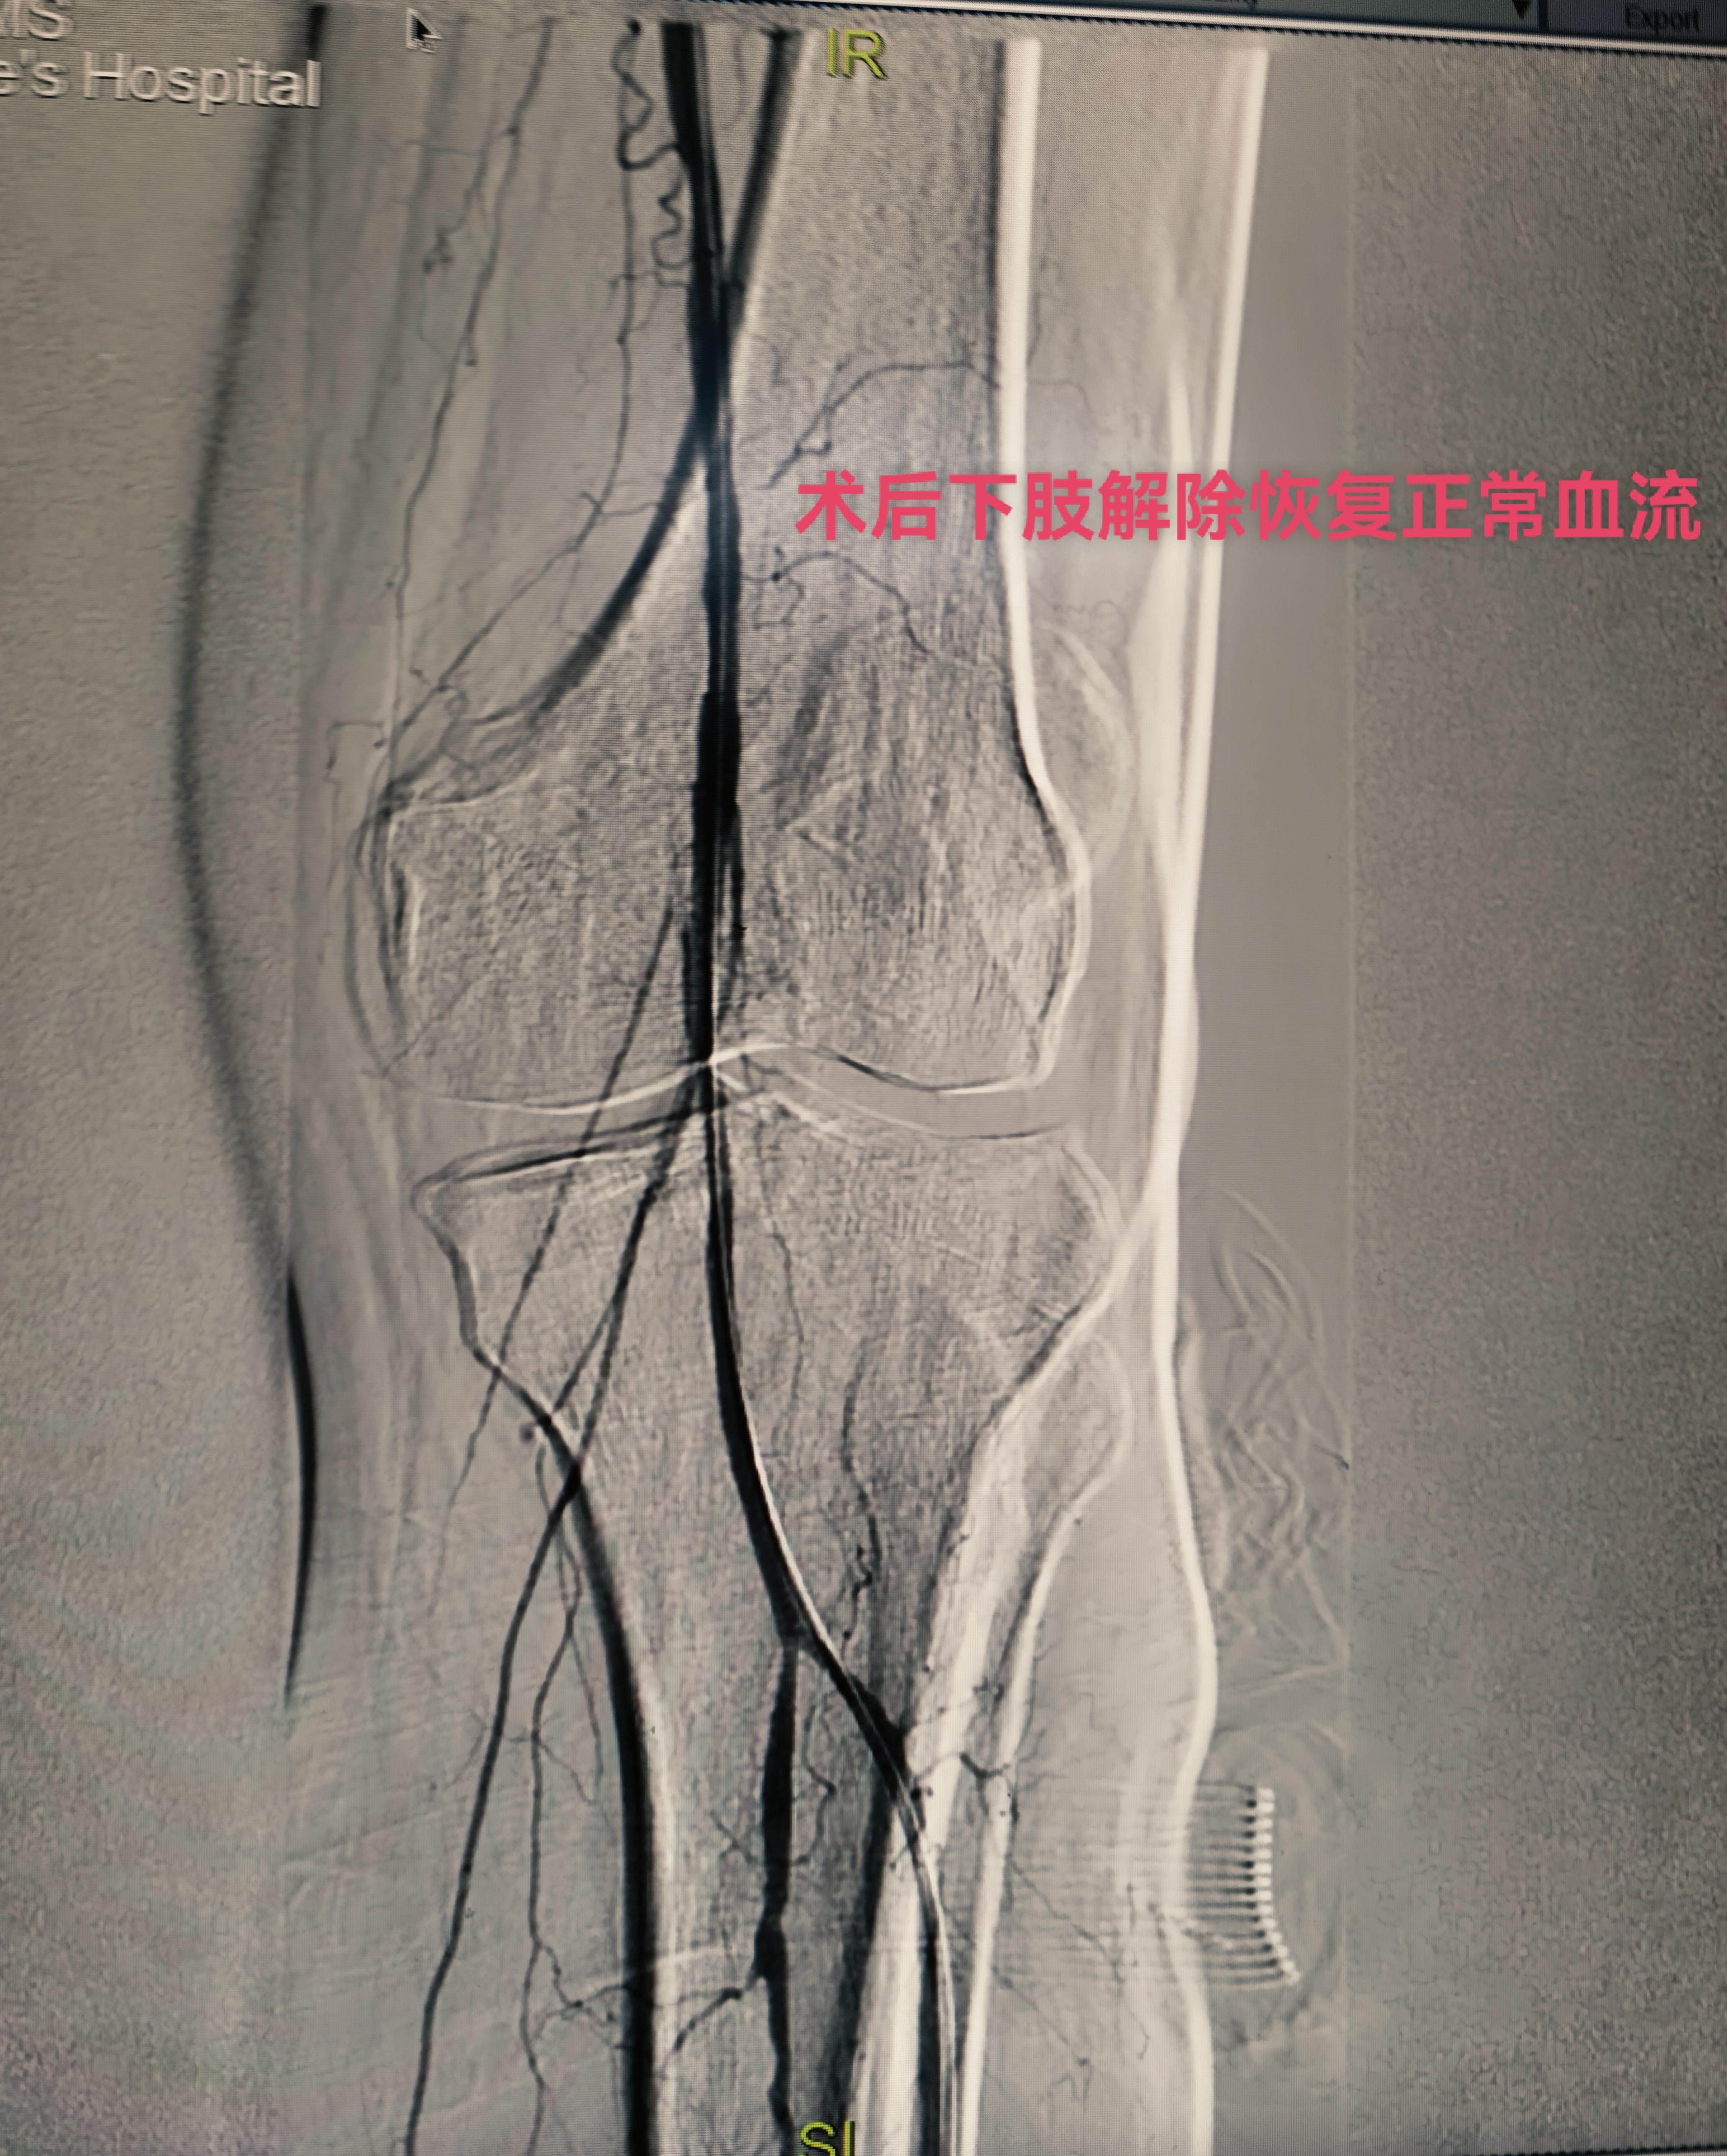

下午第一台糖尿病足三次腔内治疗再次未规律服药再次狭窄闭塞,下肢溃烂发黑,疼痛难忍。再次行球囊扩张术,术后皮温恢复,疼痛减轻。 第二台腮腺癌肝转移,经穿刺活检后证实后。行载药微球的灌注化疗栓塞。